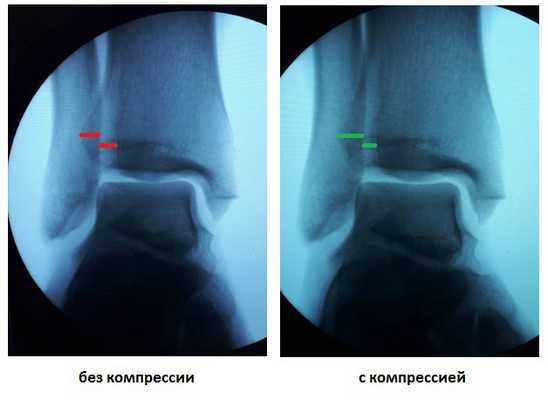

У данного пациента также определялась избыточная подвижность малоберцовой кости на уровне дистального межберцового синдесмоза при компрессии голени на уровне средней трети, которая клинически проявляется болью по переднему краю наружной лодыжки.

После восстановления латерального связочного комплекса по Брострому в модификации Голда и фиксации межберцового синдесмоза винтом производится оценка стабильности голеностопного сустава при помощи вальгус—стресс теста под контролем ЭОП.

Гипермобильность голеностопного сустава устранена, положение таранной кости остаётся неизменным несмотря на приложение вальгусной нагрузки.